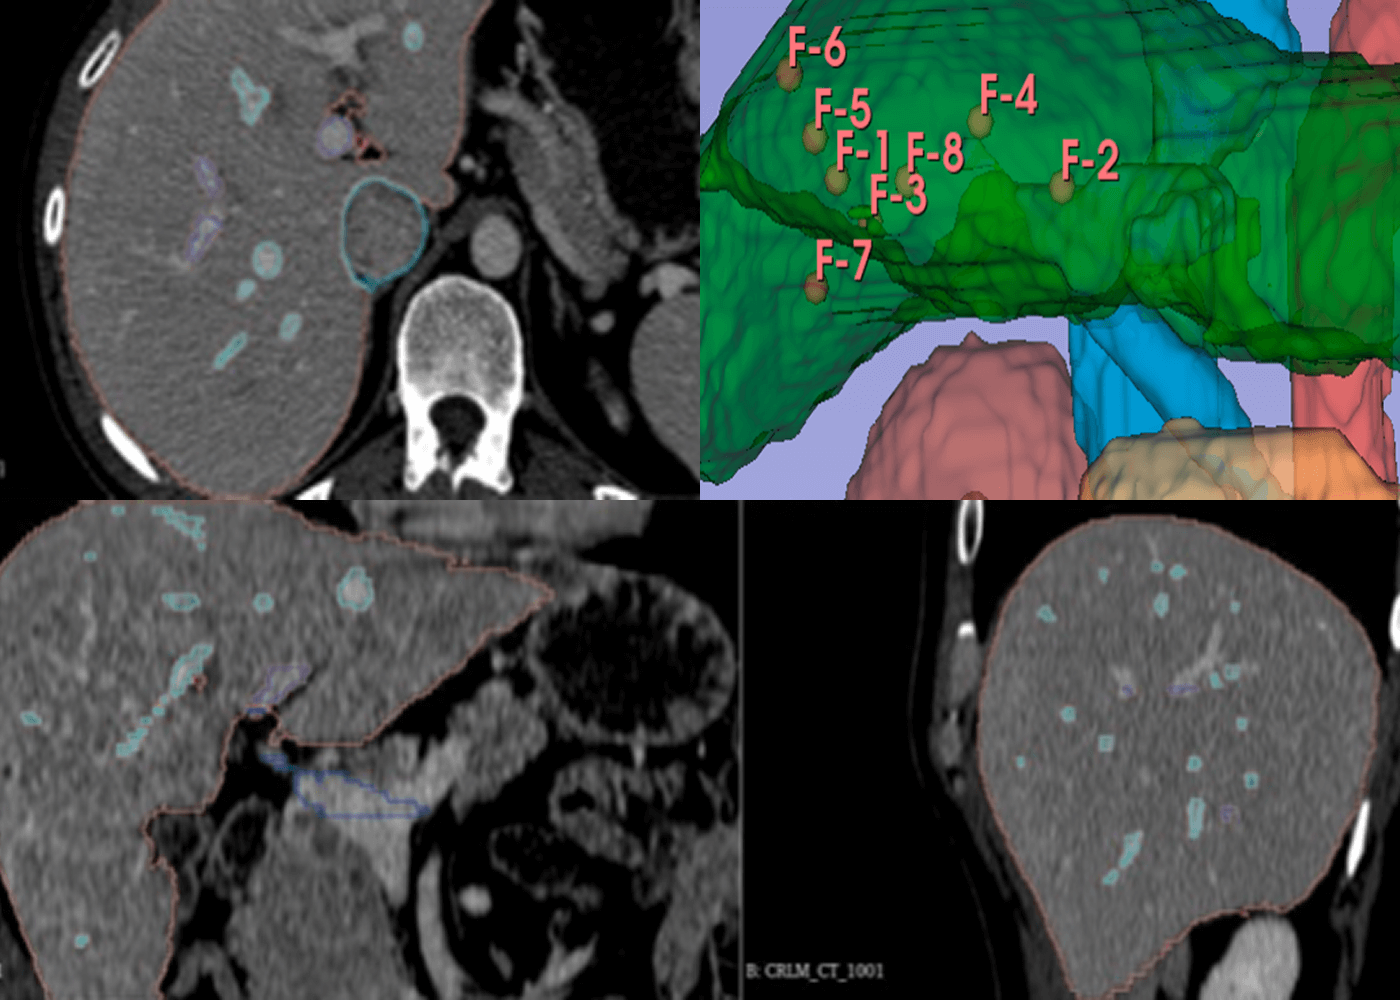

radiology

Liver with pixel perfect segmentationand point markups